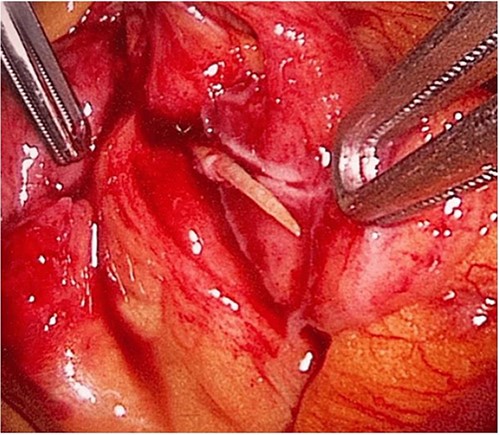

During her hospital stay, the patient showed no improvement regarding abdominal pain, nausea, or abdominal exam. Therefore, she was offered a laparoscopic exploration to verify the diagnosis of a FB to which she agreed. She was taken to the operating room, and the exploration showed an inflammatory process in the LLQ (Fig. 3) with the sigmoid colon attached to the area of the inflammatory reaction. A FB was found in the mesentery of two loops of the ileum 100 cm from the ileocecal junction (Figs 4 and 5). Removal of the FB safely and milking of the small bowel showed no leakage of bowel contents (Fig. 6). And, exploring the rest of the abdomen showed no other pathology and normal ovaries (Figs 7 and 8); the procedure was uneventful. The FB was identified as a toothpick, 3 cm in length (Fig. 9).

The laparoscopic exploration showed a FB in the mesentery of two loops of the ileum 100 cm from the ileocecal junction—upon partial exposure of the site of the toothpick.